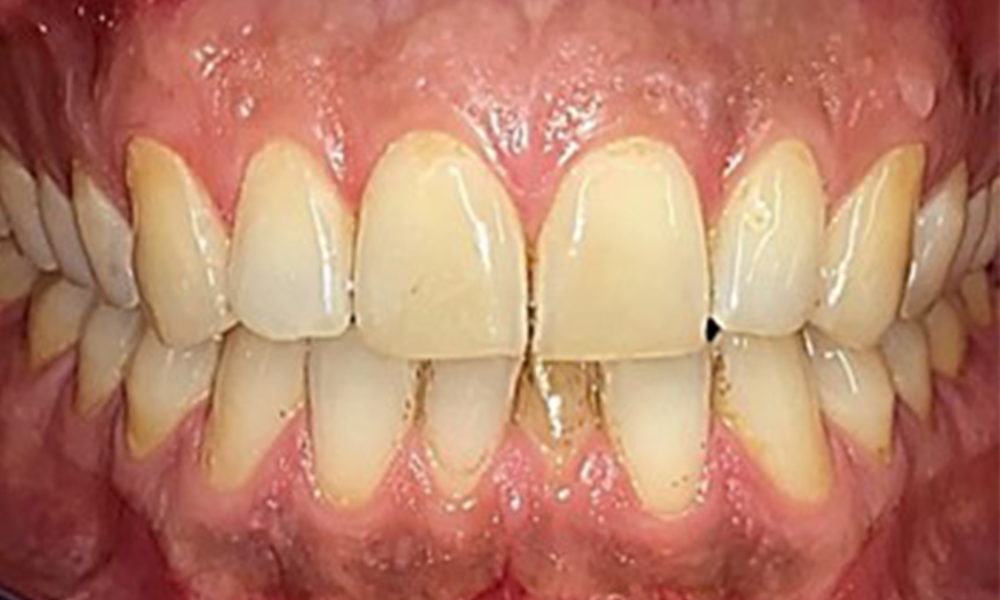

Extraoral and intraoral findings

There were no pathological extraoral findings. During intraoral examination, inspection of the frontal view revealed brownish discolouration near the keratinised gingiva and at the transition to the moveable mucosa (Fig. 2), which could be attributed to nicotine consumption. Whitish mucosal lesions were observed on the palate, particularly near the maxillary molar palatal surfaces, indicating increased keratinisation and can also be attributed to nicotine consumption. The tongue was covered with a removable white and brownish coating.